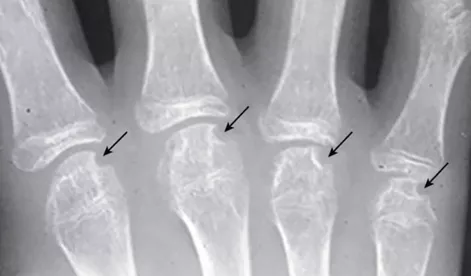

Рентгенография суставов: сужение суставных щелей и эрозии кости в лучезапястных суставах, мелких суставах кистей, стоп и плечевых суставах появляются в течение первых двух лет течения болезни. В костях запястья разрушение хряща происходит в проксимальном запястном суставе и интеркарпальных суставах, что приводит к карпальному анкилозу и укорочению конечности (фото 12). Также часто развивается атланто-аксиальное переразгибание.

Фото 11. Костные эрозии у девочки с РФ-позитивным полиартикулярным ЮИА [9].